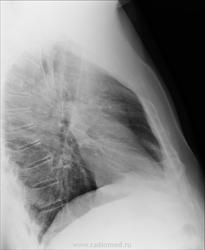

Хр. бронхит это не наше заключение. Есть усиление лёгочного рисунка обоих лёгких. В правом верхние сегмегты, есть очаговые тени слабой интенсивности. Я бы написал пневмонию. Очень характерно для вирусной.

Характерно как для бронхопневмонии, так и для Твс.) Сейчас больного дообследуем по полной!)

Пневмонии не вижу.

Тоже бы написал усиление и обогащение легочного рисунка. И порекомендовал бы R-контроль.

Это просто обогащенный рисунок, суммированный с ребрами. С другой стороны точно такой же.